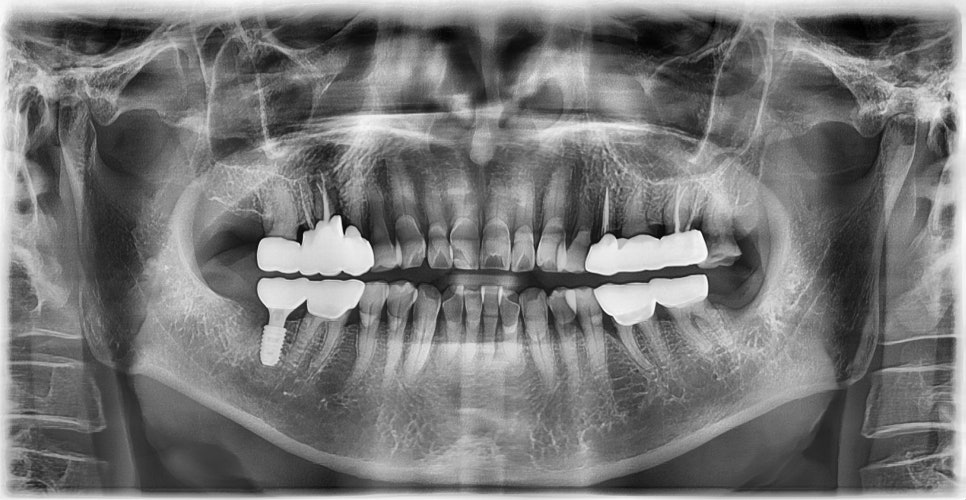

보철물 장착 (2025-5-23)

본 환자는 81세 남환으로 오른쪽 아래 어금니가 씹을 때 아프고 찬물에도 시리다며 내원하셨습니다. 고혈압 병력이 있으셨으며 혈압조절 목적으로 매일 혈압약 복용중이라고 하셨습니다.

초진 X-ray (2024-8-16)

치아 발치시 지혈에 큰 문제가 없어 내과 협진 후 고혈압약은 중단하지 않고 임플란트 수술 진행하기로 하였습니다. 수술 후 통증도 없고 지혈도 잘 되어 환자분께서 너무 만족하셨습니다. 감염 예방 목적으로 처방해드린 약은 모두 복용하시도록 안내드렸습니다. 임플란트 수술 약 3달 후 보철물을 장착하였습니다.

임플란트 픽스쳐 식립 (2024-8-27)

보철물 장착 (2024-11-5)